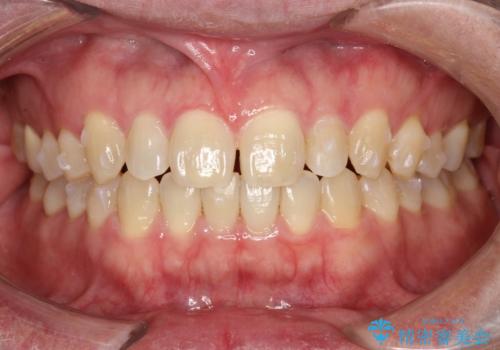

前歯の真ん中の隙間を閉じたい インビザラインによる目立たない矯正

- 上顎の正中の隙間が気になるとのことで来院されました。

下の歯と歯の間をわずかに削り、スペースを作り、正中の隙間を閉じる計画としました。

装置はインビザラインにて行いました。

インビザラインで目立たずに矯正治療を行うことができました。

使用時間を守っていただけたので、比較的スムーズに矯正を終了することができました。